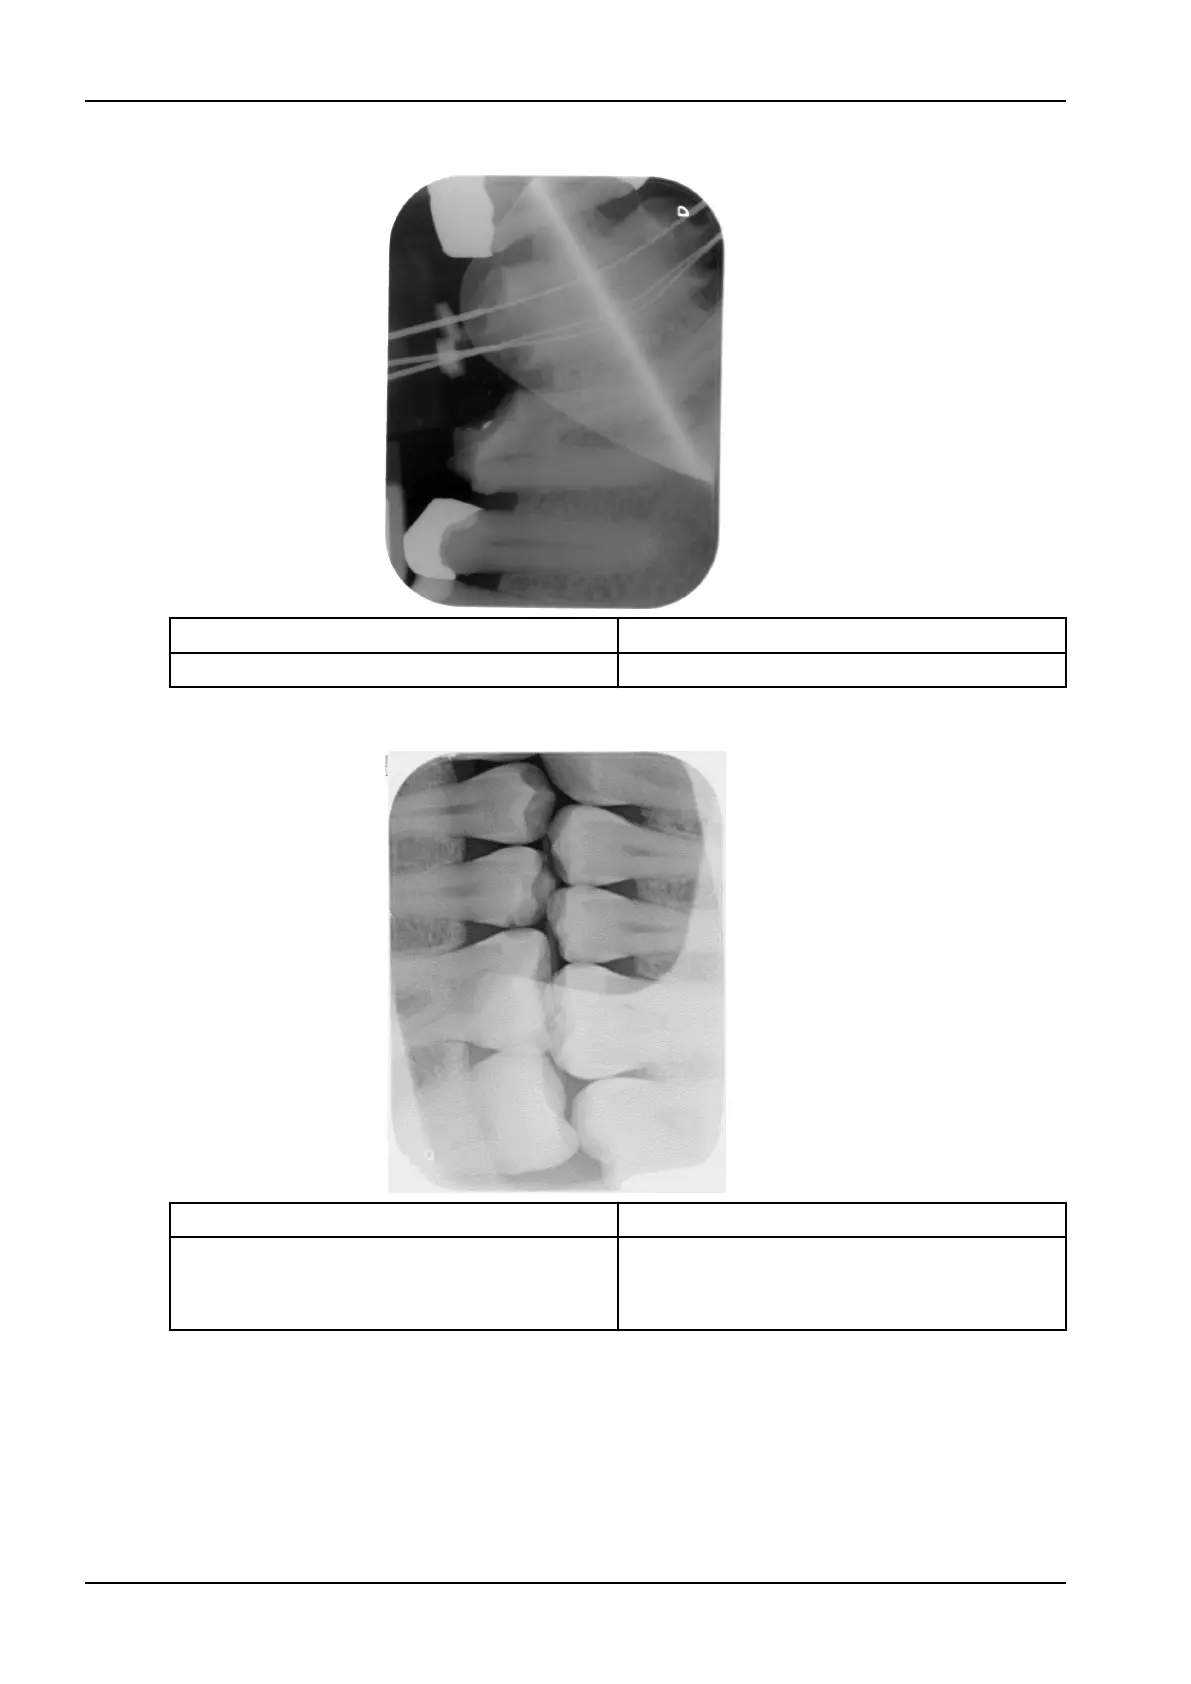

X-ray image mirrored in one corner

Possible cause Remedy

Image plate bent during X-ray exposure Do not bend the image plate.

Shadow on X-ray image

Image plate removed from the light protection

cover before scanning

Do not handle image plates without a light

protection cover.

Store the image plate in a light protection cover.